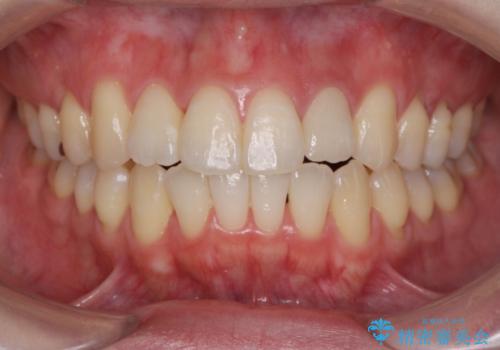

【非抜歯】インビザラインで正しい噛み合わせを

前歯のガタつきを治したい 翼状捻転マウスピース矯正

【インビザライン】がたつきをマウスピースできれいにしたい